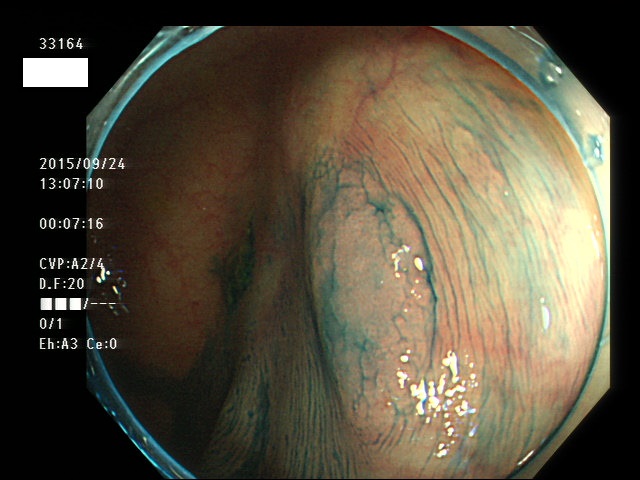

上記100名より抽出した平坦・陥凹型腺腫(=癌化の危険が高いが見落としやすい病変)の内視鏡写真